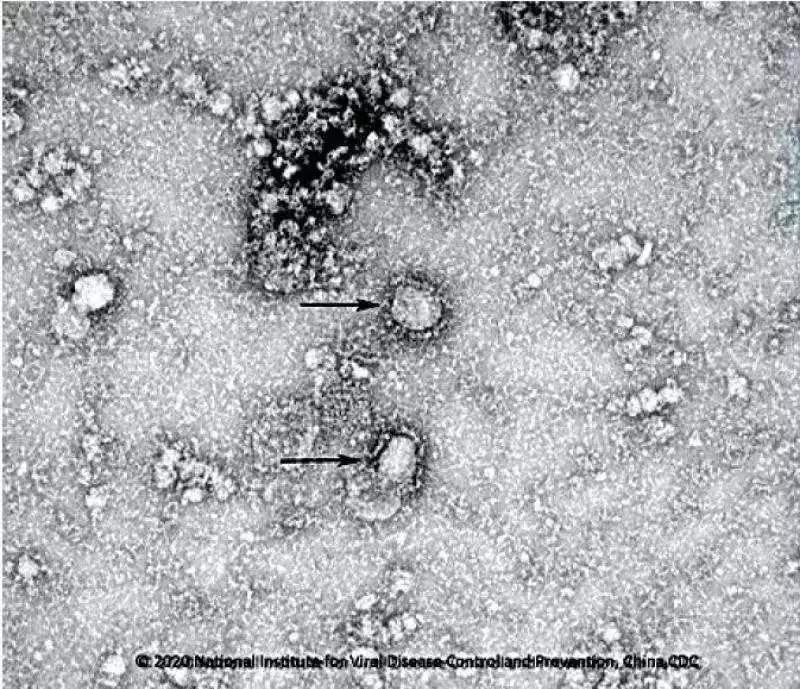

中国疾控中心已成功分离我国首株新型冠状病毒毒种

中国疾控中心病毒所所长许文波26日对记者表示,目前该中心开始启动新型冠状病毒的疫苗研发,目前已经成功分离病毒,正在筛选种子毒株。

此外,中国疾控中心正在进行新型冠状病毒肺炎的药物筛选。